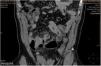

However, he returned to the Emergency Department six hours later due to diffuse abdominal pain of an increasing intensity, as well as abdominal distension. His blood tests revealed leukocytosis with neutrophilia and elevated CRP levels. A chest X-ray was performed that showed pneumoperitoneum. The abdominal CT scan (Fig. 1) showed pneumoperitoneum predominantly in the hypogastrium/right iliac fossa, in close association with ileal bowel loops that exhibited inflammatory changes, as well as dense areas and locoregional fat involvement. In addition, a diverticular image with intense enhancement and wall thickening of the distal ileal loop was identified, consistent with acute perforated Meckel's diverticulitis. The patient underwent emergency surgery, confirming the finding of Meckel's diverticulitis with local inflammatory signs as well as secondary peritonitis, which was resected. The patient was discharged five days later. The pathology results revealed a diverticular formation with mucosa of gastric appearance, as well as a perforated area of the mucosa, although the biopsy did not clearly identify diverticular inflammation but rather surrounding acute purulent peritonitis.